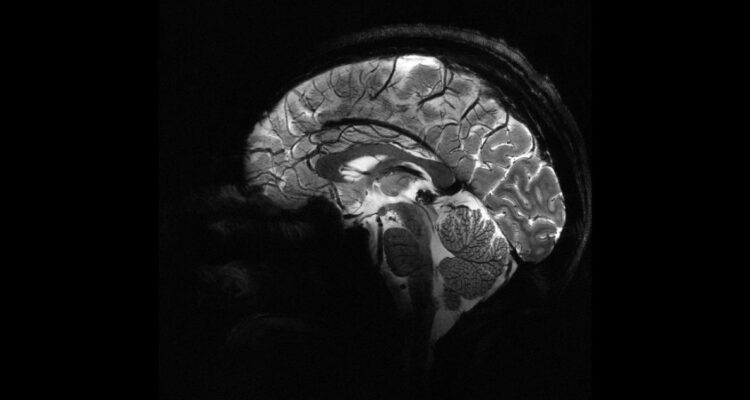

La Comisión de Energía Atómica (CEA) de Francia, reveló esta semana las primeras imágenes del cerebro humano tomadas con el escáner de resonancia magnética más potente del mundo.

Isault sólo tardó 4 minutos en hacer el escáner, que resultó en las imágenes atómicas más notables del cerebro en la historia. “Las imágenes tienen una resolución impresionante para un tiempo de adquisición tan corto: resolución en el plano de 0,2 mm y grosor de corte de 1 mm, lo que representa un volumen equivalente a unos pocos miles de neuronas”, describe el organismo.